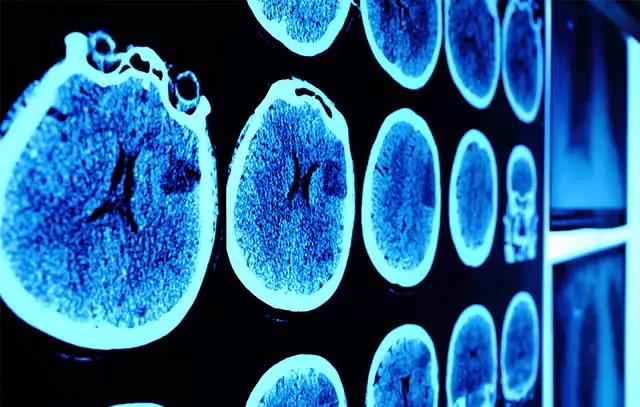

Brain cancer: That’s a really scary term. Luckily, there’s a less than 1 percent change you’ll develop a malignant brain or spinal tumor in your life, according to the American Cancer Society. Still, the ACS estimates that about 23,890 cases of brain cancer will be diagnosed in 2020 (and an estimated 10,300 of those will be in females). And, get this, the current average survival rate for brain cancer is 36 percent, according to information from the National Brain Tumor Society updated this year. So it can’t hurt to brush up on your brain cancer knowledge, right?

Brain cancer comes in two varieties: Primary tumors, which start in the brain and rarely spread, and secondary tumors, which start elsewhere in the body (typically the lungs or breasts) and spread to the brain, says Adilia Hormigo, M.D., Ph.D., director of neuro-oncology at the Mount Sinai Health System and associate professor of neurology, medicine and neurosurgery at the Icahn School of Medicine at Mount Sinai.

Over time, brain cancer can impact surrounding brain cells to seriously compromise brain function. And while that's true of all brain tumors, malignant or benign, cancerous tumors are more likely to spread throughout the brain, and quickly, according to Hormigo. That's why malignant tumors require aggressive treatments, typically including surgery, radiation, and/or chemotherapy, she says.